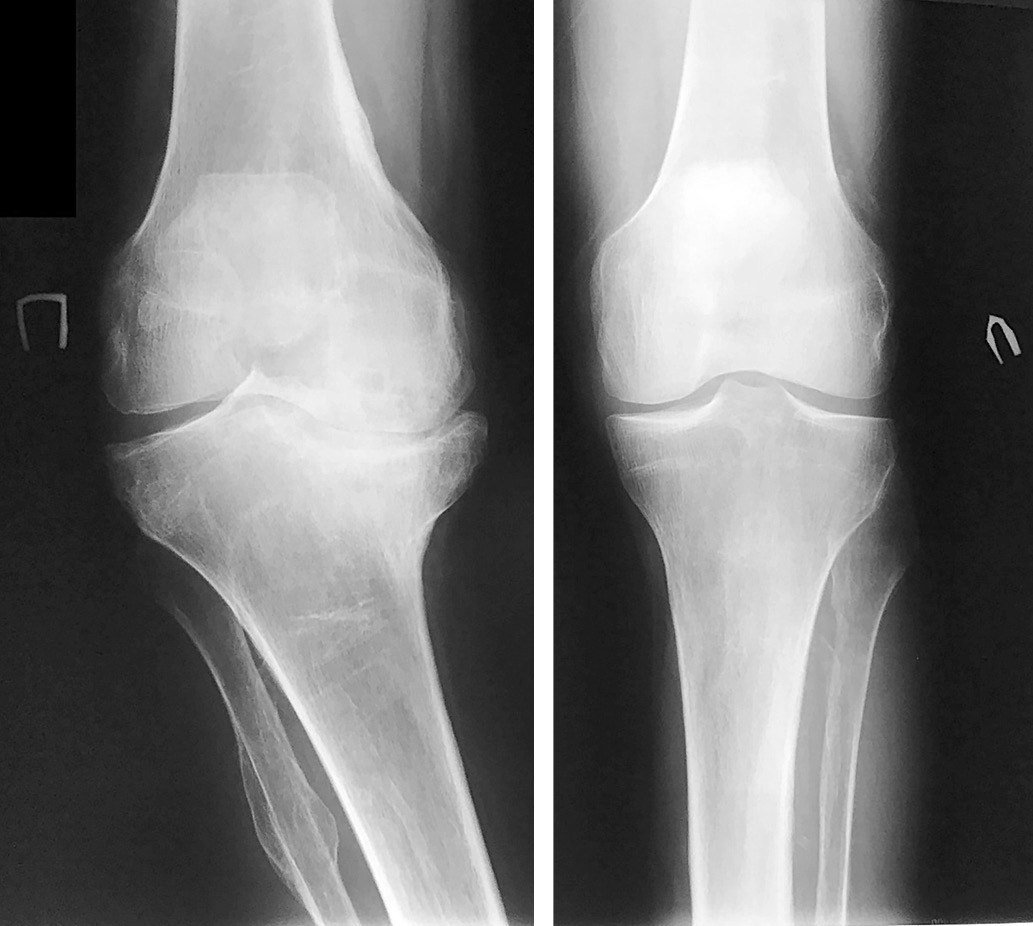

На рентгенограммах коленных суставов (рис. 8) травматический подвывих справа бедренной кости, большеберцовой с признаками двигательной нестабильности в суставе, хронический бурсит задне/наружного квадранта. Слева – средневыраженный артроз с ротационным подвывихом.

Рис. 8. Рентгенограмма обоих коленных суставов при поступлении, 2018 г.

На рентгенограммах локтевых суставов (рис. 9) – картина хронической стадии ДНОАП с обеих сторон.

Рис. 9. Рентгенограммы локтевых суставов при поступлении, 2018 г.